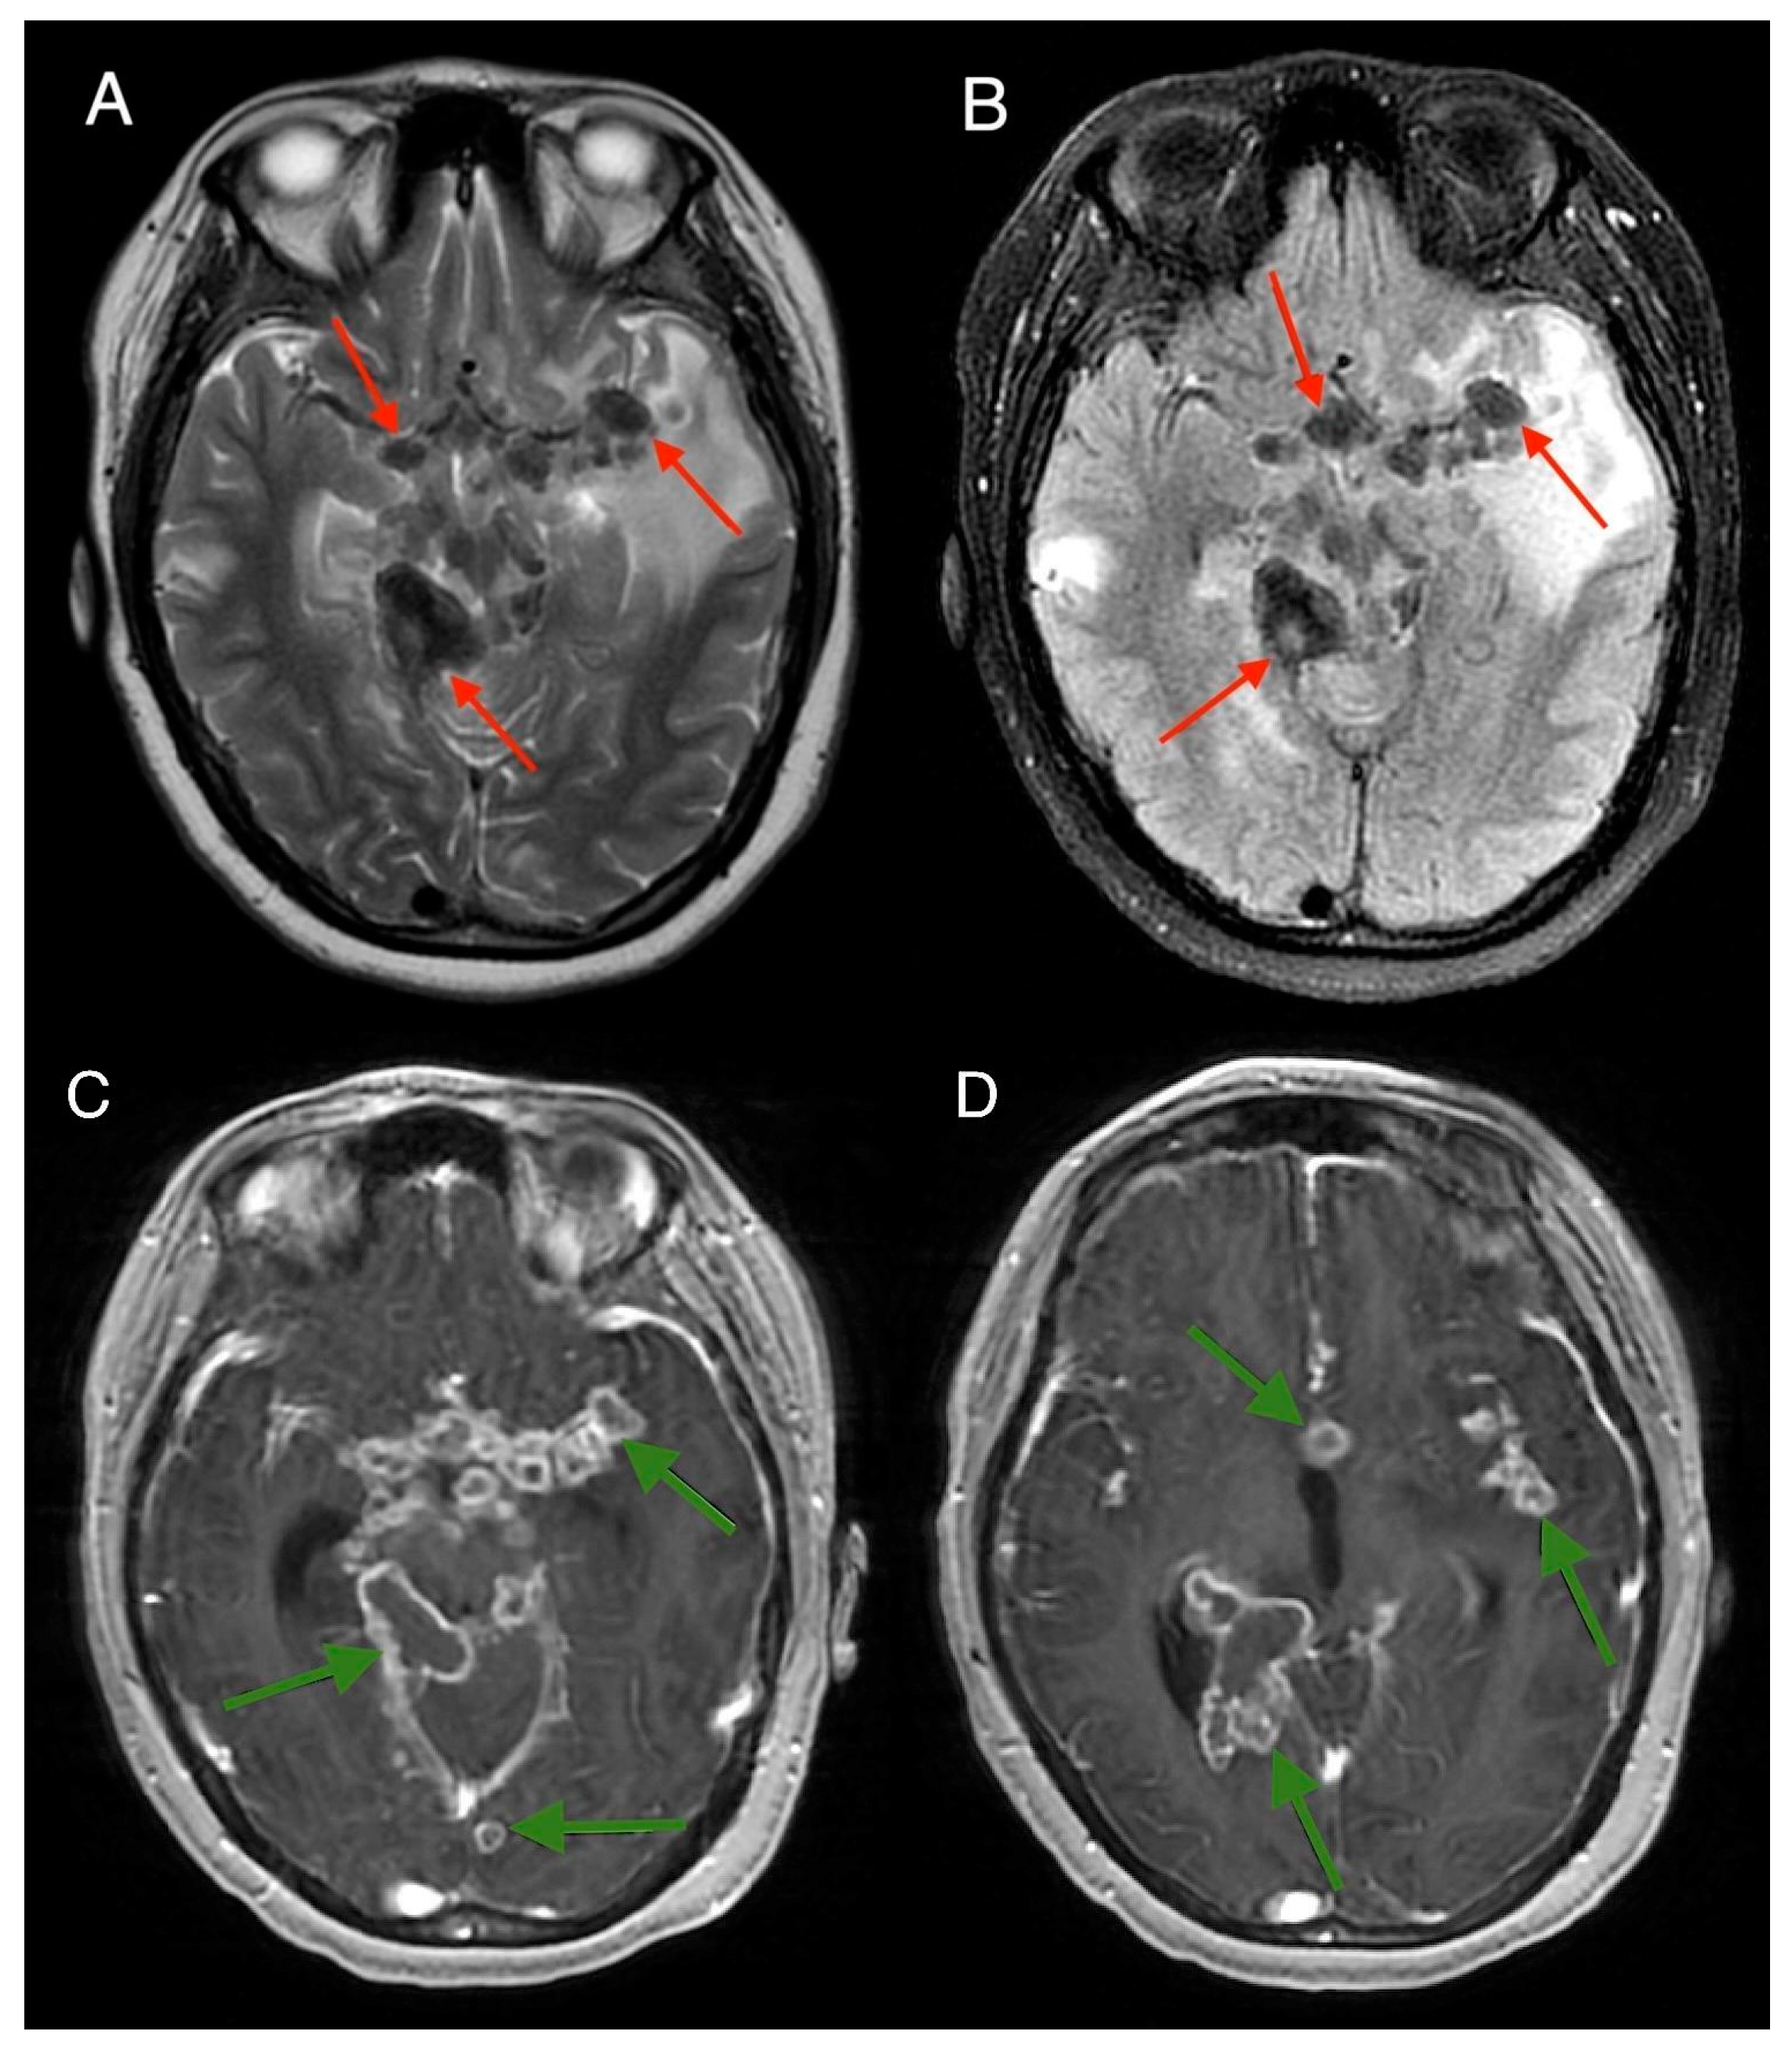

2. Case Report